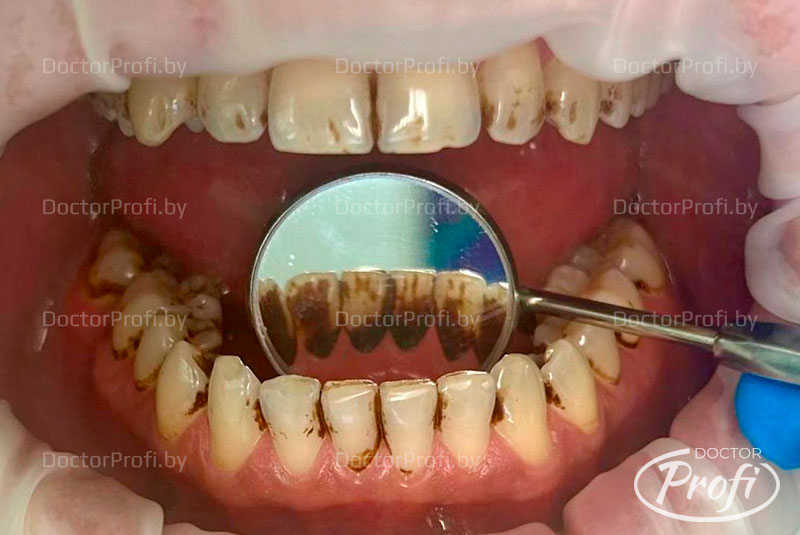

Пациент обратился клинику с желанием сделать профессиональную гигиену полости рта и устранить зубной налет, образовавшийся в результате курения.

До